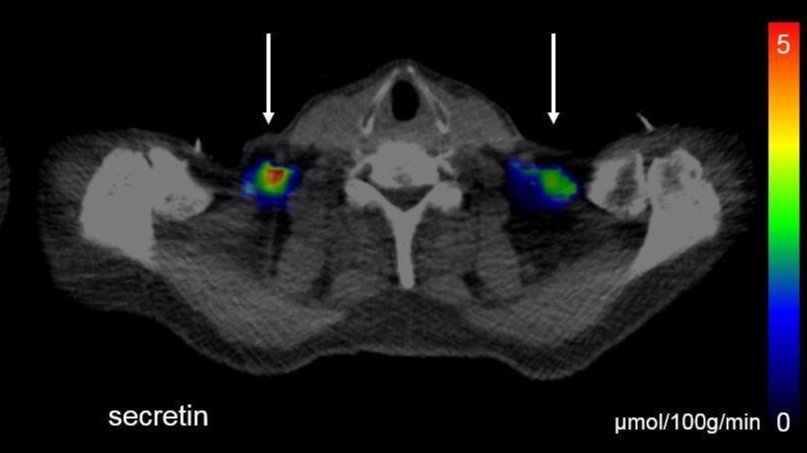

Bildgebendes Verfahren zeigt Stimulation durch Sekretin. S. Laurila

Bildgebende Verfahren zeigen, wie braunes Fett in einem Depot über dem Schlüsselbein durch das Hormon Sekretin stimuliert wird.

„Das deutet darauf hin, dass Sekretin auch das braune Fett beeinflusst. Sekretin-Infusionen steigerten in unseren Studien nicht nur die Glukoseaufnahme im braunen Fettgewebe, sondern erhöhten auch den Energieverbrauch im ganzen Körper“, sagt Wissenschaftlerin Sanna Laurila von der Universität Turku.